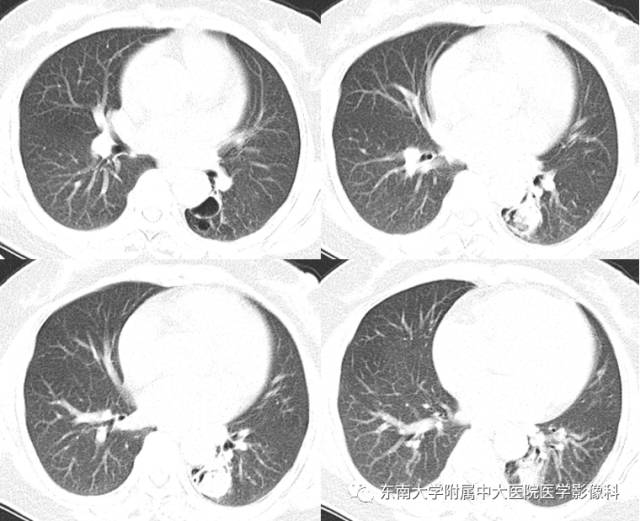

【病例】左下肺支气管囊肿伴肺曲霉菌感染

女,61岁,因“体检发现左肺占位1月余”入院。

CT